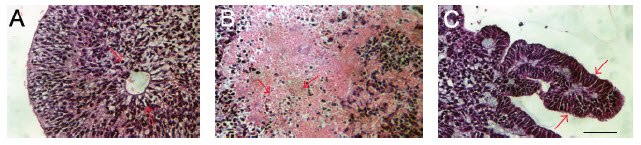

Figure 5.Whole teratoma derived from injection of PSC under the kidney capsule (A). Images of hematoxylin and eosin stained teratoma assay sections containing mesoderm (B, C), endoderm (D), and ectoderm (E, F). Image from16. Scale bar = 100 μM.

Figure 6.Sections of EBs stained with hematoxylin and eosin illustrating differentiation into ectoderm (A), mesoderm (B), and endoderm (C).17